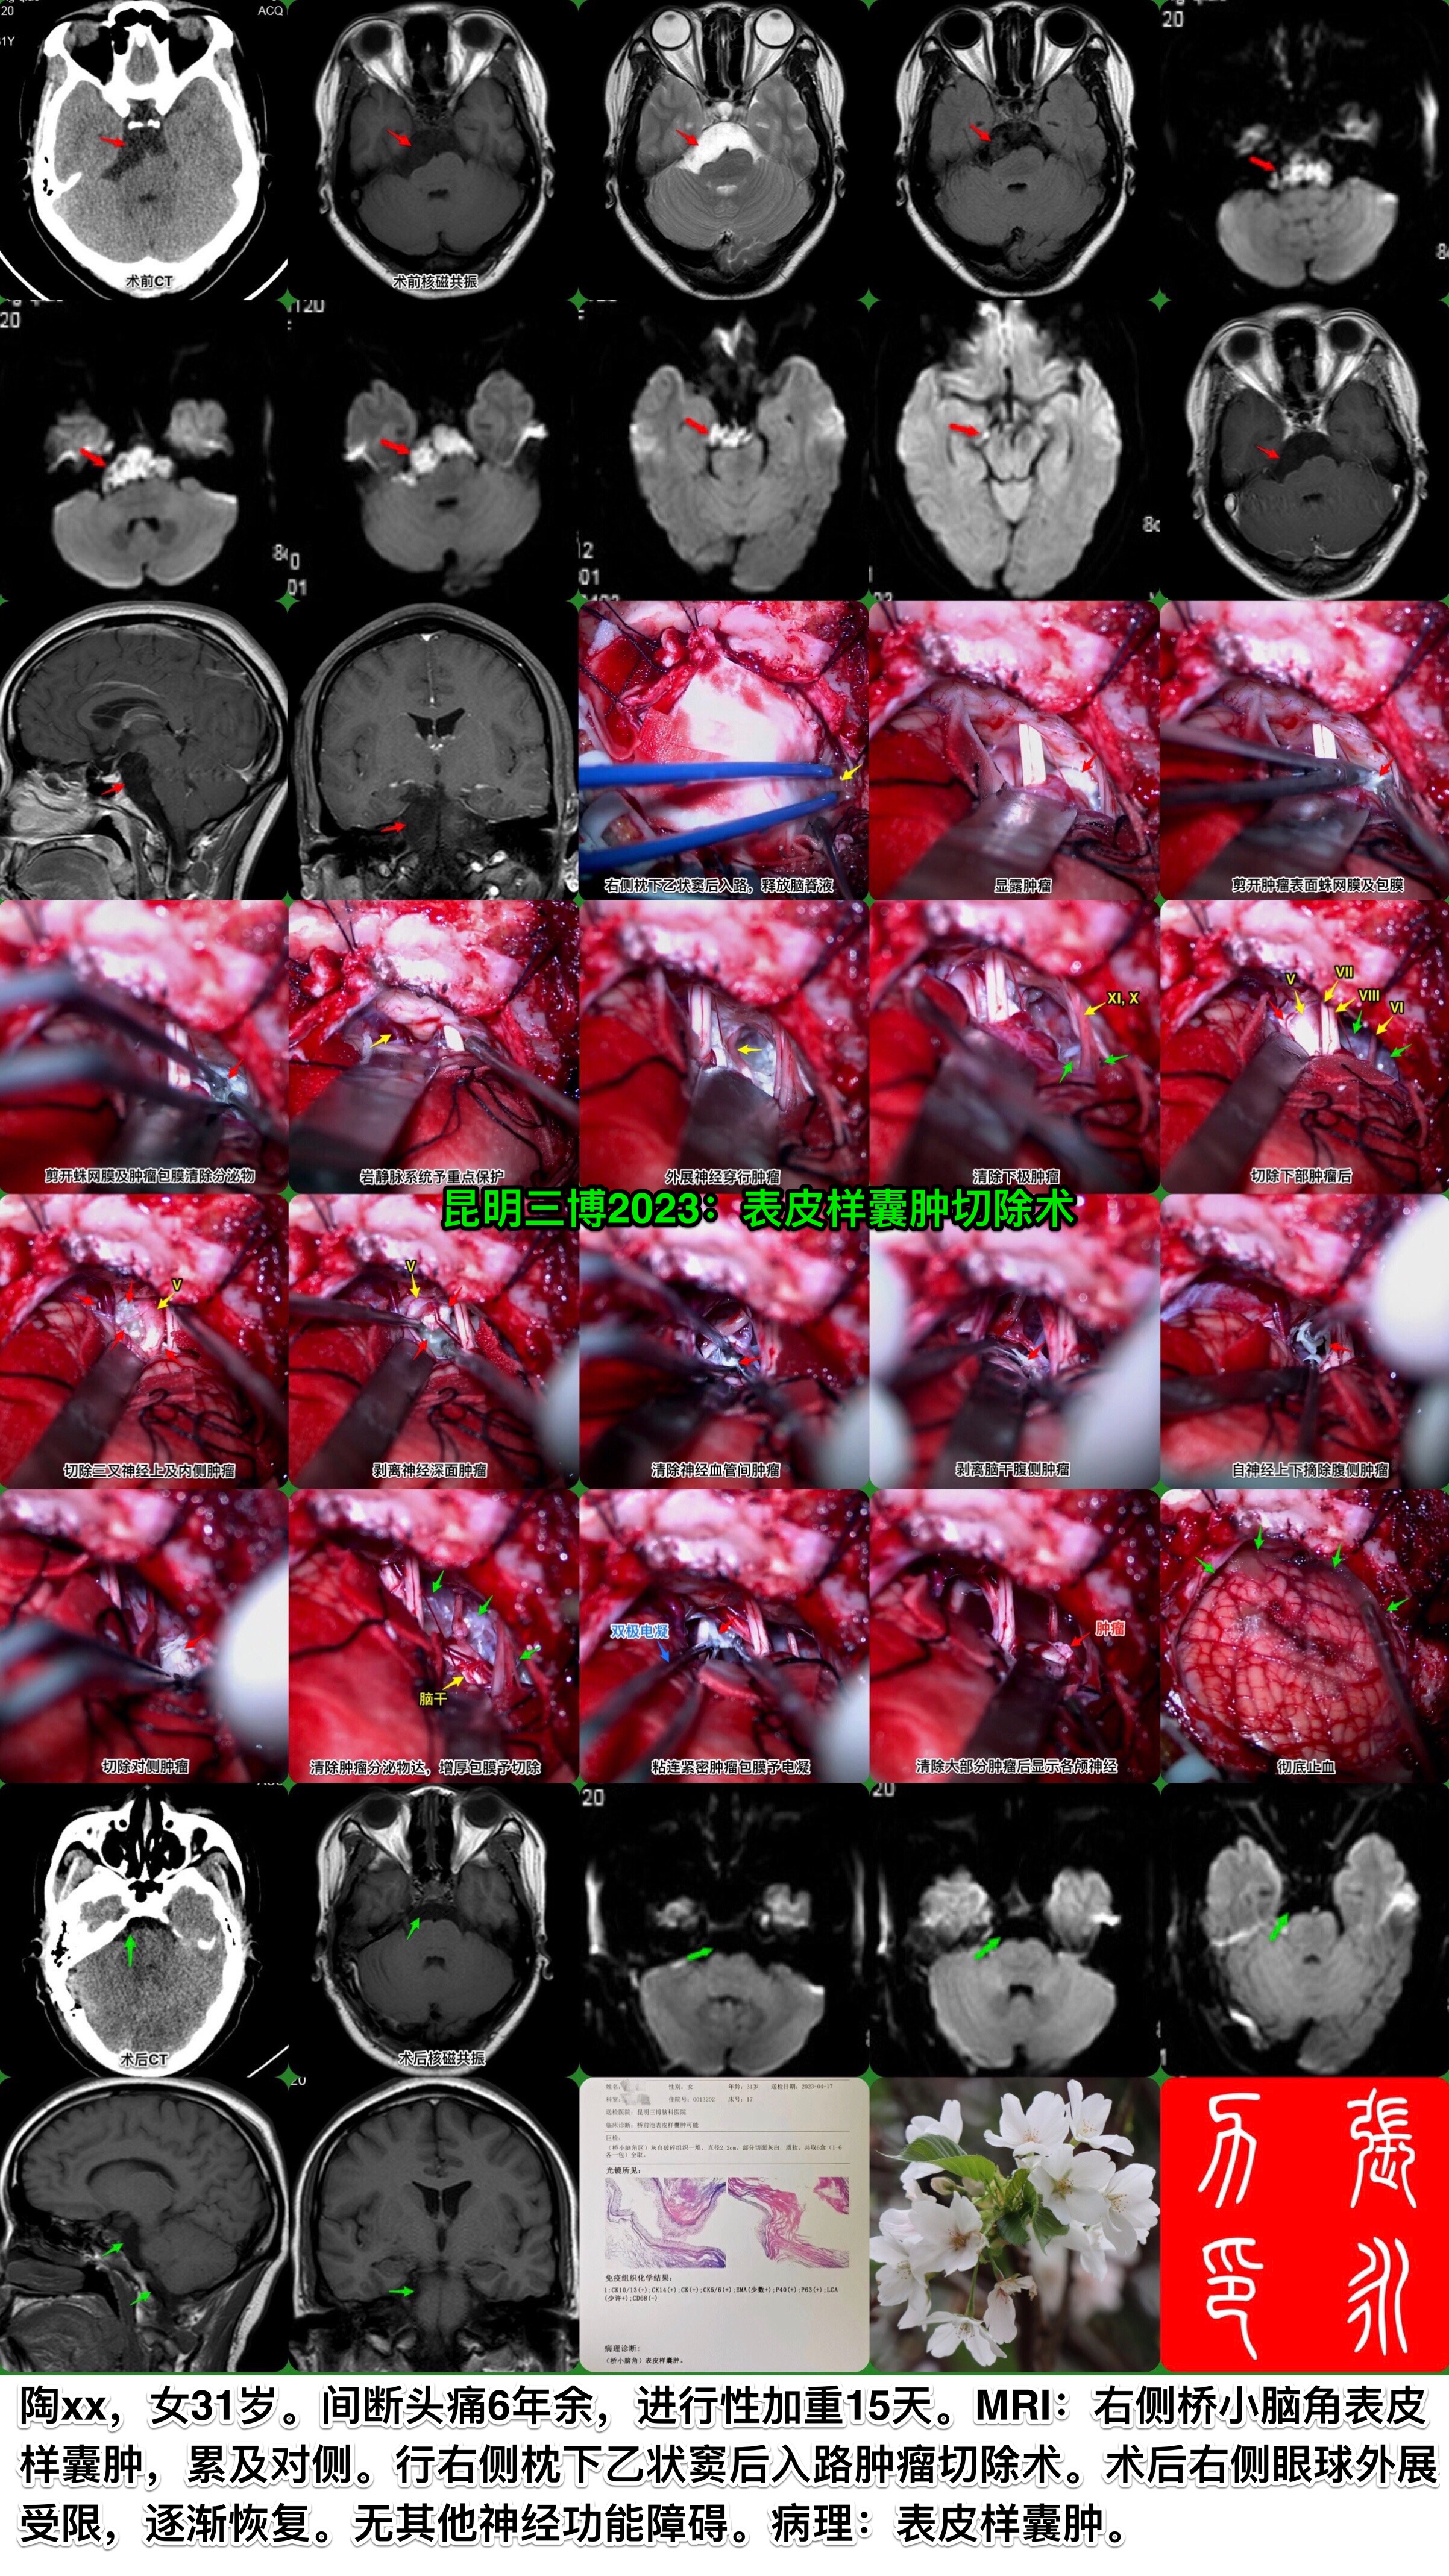

昆明三博2023:表皮样囊肿切除术

脑肿瘤-皮样囊肿/表皮样囊肿